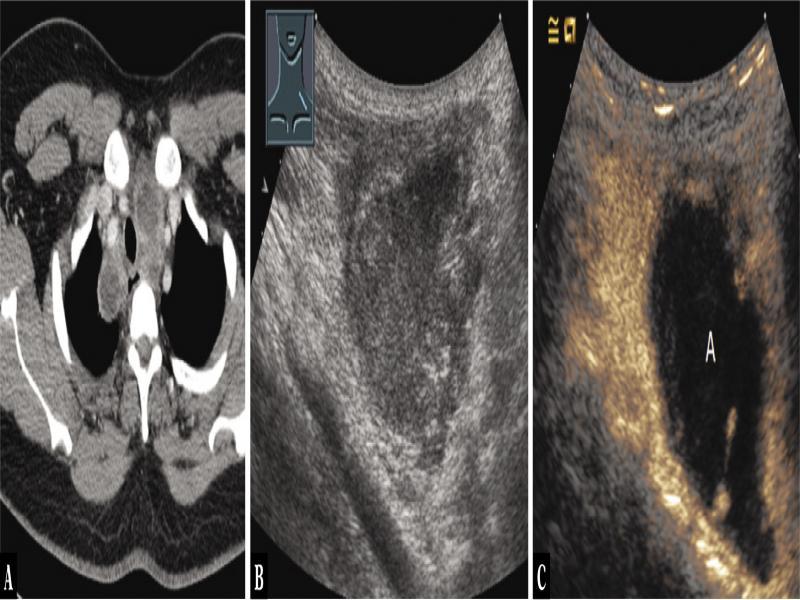

Fig. 5.

A 24-year-old male patient with dyspnea and mediastinal tumor (arrow) in the anterior mediastinum as an incidental finding on computed tomography, admitted for ultrasound-guided biopsy (A). Thoracic ultrasound indicated an inhomogeneous, hypoechoic mass (B). On contrast-enhanced ultrasound, large areas showed no enhancement with motion artifacts in real-time examination, as in abscess (A) (C). Ultrasound-guided biopsy was performed. Histologically, granulomatous necrotizing lymphadenitis was found, consistent with lymph node tuberculosis